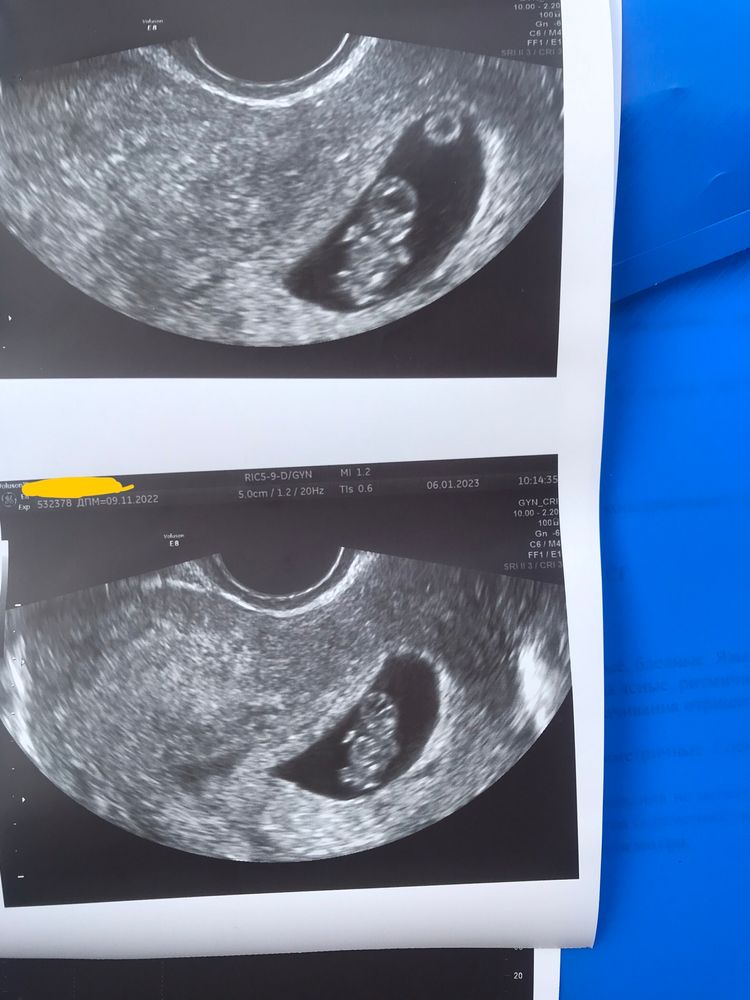

И вот наступает день Х - контрольное УЗИ.

В регистратуре вижу знакомую со времен студенчества и перекинувшись парой стандартных фраз иду с надеждой на хорошие новости, смотреть очередную часть «самого интересного фильма», не позабыв вместо попкорна прихватить с собой такого же взволнованного как и я супруга.

Малышик уже подрос и стал целых 19 мм и срок нам поставили нынче аж на один день больше - целых 8 н. 3д))) ПЯ (36 мм) было расположено в верхнем отделе, по средней линии, так же врач показала, на желточный мешок, который почему то был намного выше малышика. Скорее всего так запечатлилось в «определенном разрезе», к примеру, на фото с гематомой, малышик выглядит какой то непонятной субстанцией, а там где основной фокус был на плоде мы с супругом отчетливо видели маленькую матрёшечку которая очень даже активно двигалась. Можно было уже разглядеть не просто голову и туловище, но и ручки с ножками)))) Послушали сердечко (176 уд. в мин).

Это все конечно ми-ми-ми, но интересовали меня больше гематомы.

- Ну вот! - Удовлетворительно подводит итог УЗИст. - Та, гематома, что была по передней стенке, смотрите, - настраивает аппарат и указывает на тоненькую полосочку, - Размером с волосок стала. Ее можно уже не учитывать. Вторая стала больше (23*11 мм), но это и понятно, матка растет, а вместе с ней и гематома растягивается, в этом нет ни чего страшного, тем более что она уже на стадии организации.

- Значит, что тоже скоро исчезнет. - Поясняет врач. - Ребенок у Вас такой активный! Может Вы и не заметили, но я видела какой он там подвижный.

Выкатывает результаты УЗИ и так же делает отдельно два снимка для нас.